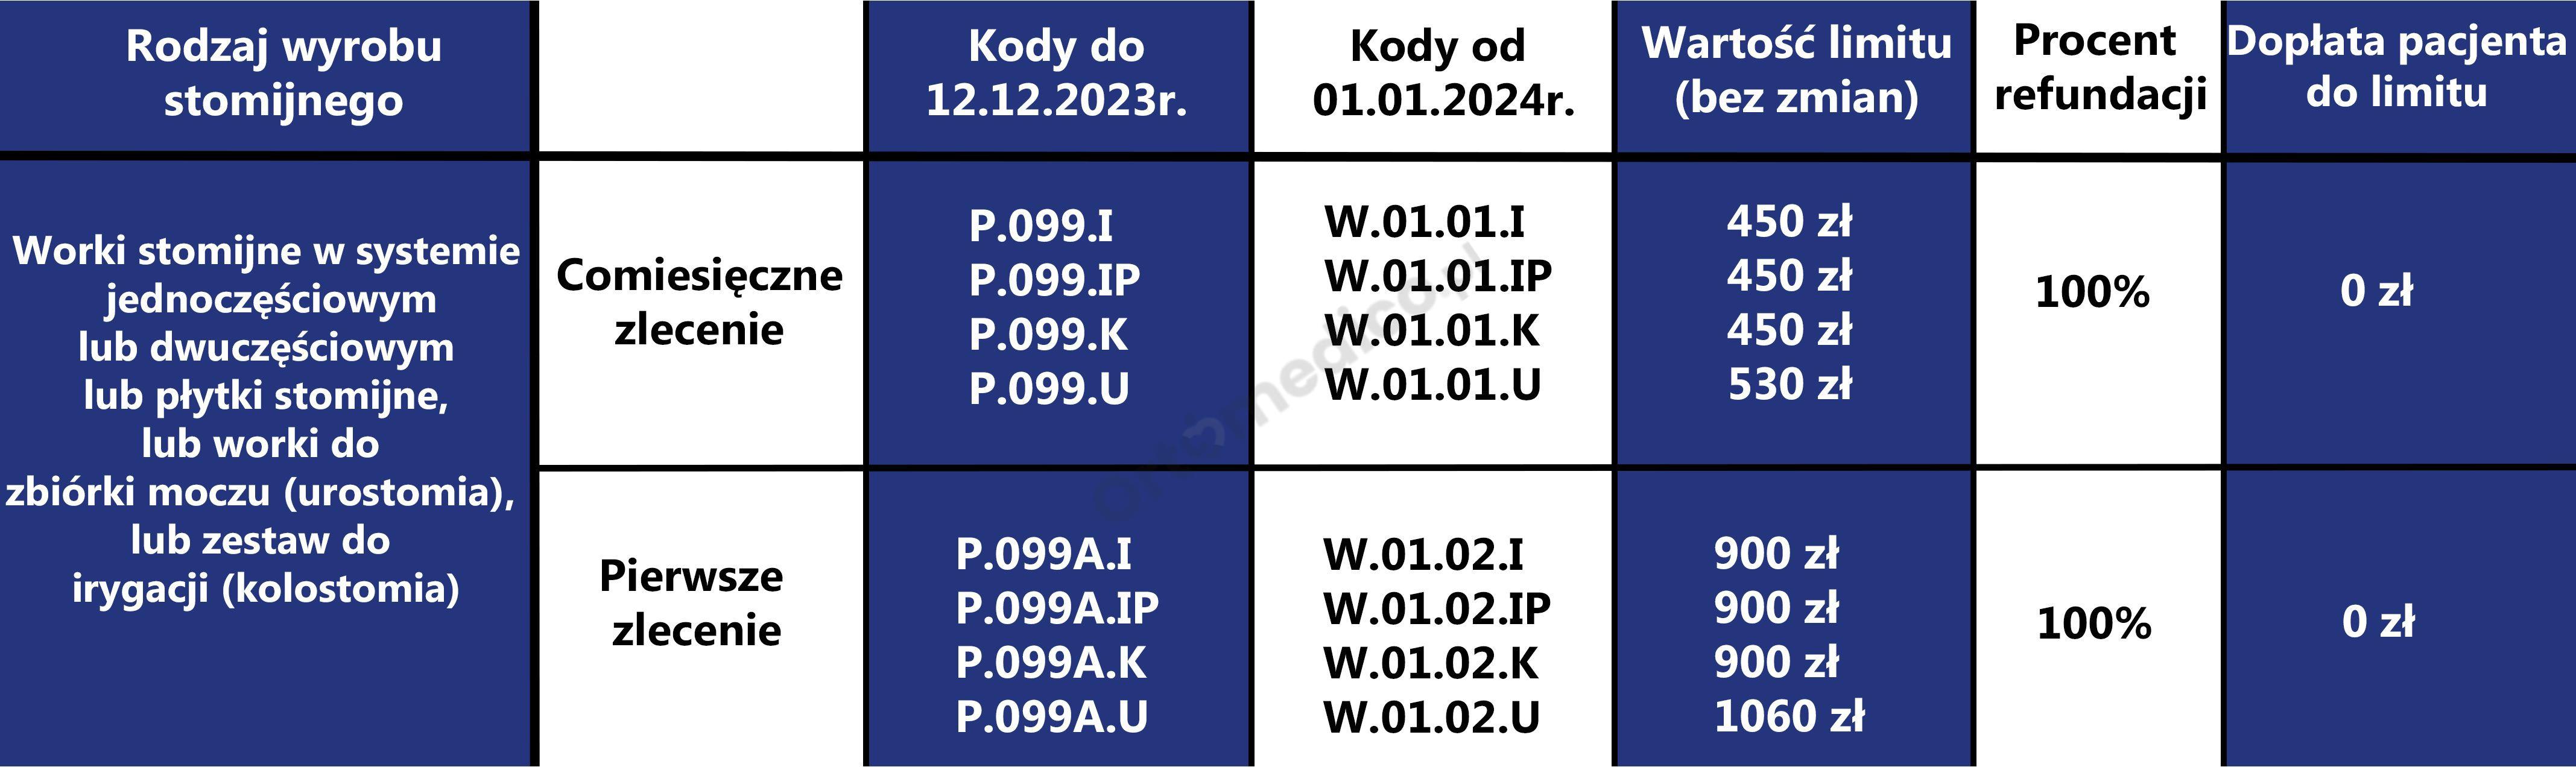

Od 1 stycznia 2023 roku zmianie uległa refundacja wyrobów stomijnych. Ustanowiono 2 zlecenia na sprzęt stomijny (P.99 worki i płytki i P.141 akcesoria) oraz osobne zlecenie (P.99.A, P.141.A) dla pacjentów nowo operowanych z podwójnym limitem. Podwyższono limity: w kolostomii i ileostomii do 450 zł ; w urostomii do 530 zł, akcesoria 120 zł w tym 20% dopłaty pacjenta. Wystawiający zlecenie będzie zlecał ryczałt lub jego część lub jego wielokrotność w przypadku pacjentów z 47ZN, 47ZND, 47DN.

Od 1 stycznia 2024 roku będą obowiązywały nowe zasady refundacji wyrobów stomijnych przez Narodowy Fundusz Zdrowia. Zgodnie z rozporządzeniem Ministra Zdrowia z dnia 13 października 2023 r. zmieniającym rozporządzenie w sprawie wykazu wyrobów medycznych wydawanych na zlecenie kwoty limitu pozostają bez zmian, zmienia się natomiast udział pacjenta w limicie w wyrobach stomijnych dla osób dorosłych i dzieci do 18. roku życia.